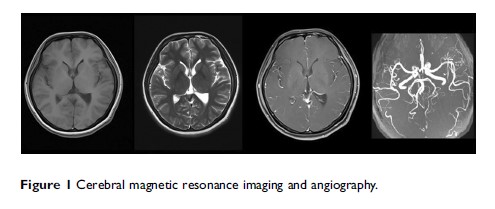

舞蹈病和利用类固醇治疗患有神经功能缺损和脑脊液淋巴细胞增多症的短暂性头痛综合征患者的有效性:病例报告